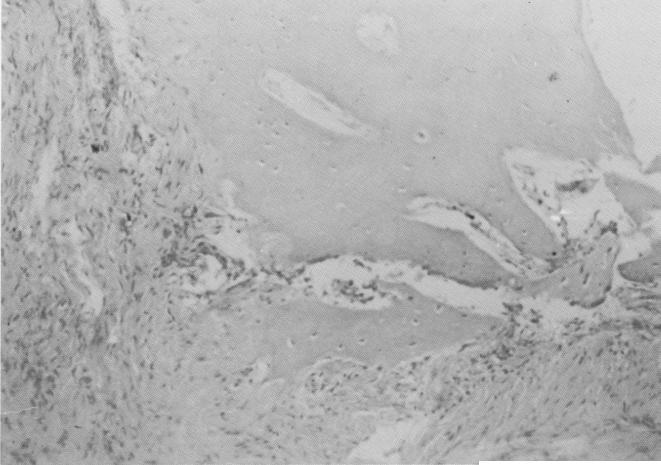

Fig. 4-51. That part of the soft tissue specimen away from the implant site contains numerous islands of bone.

Fig. 4-52. Under higher magnification the bone fragments are seen to contain numerous osteocytes.

1 Soft tissue near vent plant implant site shows many islands of bone

2 Histology of vent plan implant site shows bone fragment with osteocyte